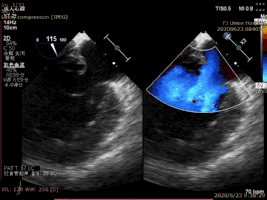

病例1術(shù)前二尖瓣反流為重度